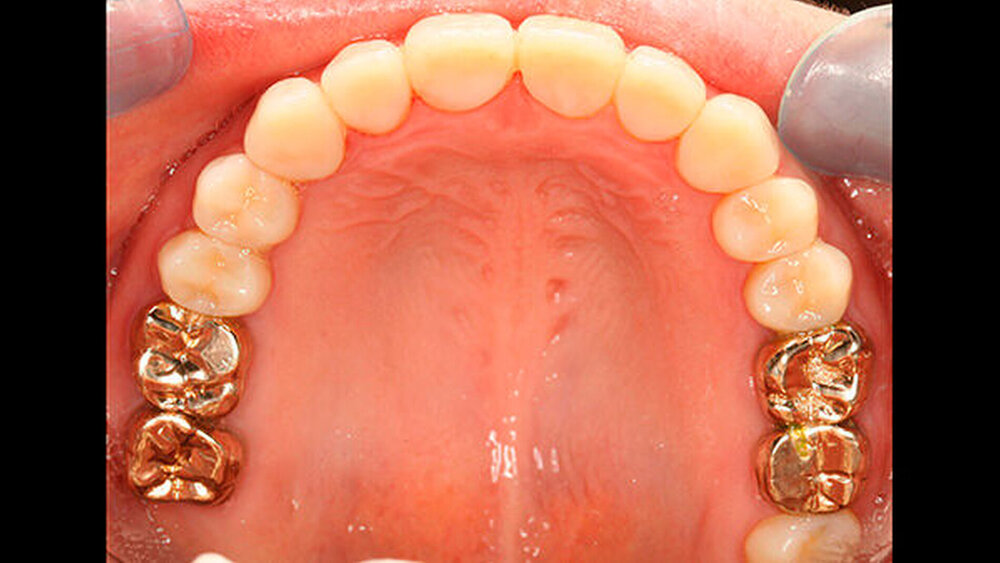

Bisher war die Patientin größtenteils mit provisorischen Maßnahmen behandelt worden. Eine Ausnahme bildeten hier die Sechsjahrmolaren, die ihrzufolge sehr zeitnah nach vollständigem Durchbruch mit Goldteil- beziehungsweise -vollkronen versorgt wurden. Im Oberkiefer wurden später auch für die zweiten bleibenden Molaren Vollkronen gewählt (Abbildungen 1 und 2).

Abbildung 1 gibt einen guten Überblick darüber, dass teils mehrere Restaurationen pro Zahn durchgeführt wurden und die dazwischen verbliebenen Bereiche aus Zahnschmelz oft nur gering waren (insbesondere an den Frontzähnen). Gleichzeitig zeigt aber auch der Vergleich der kontralateralen Prämolaren, wie anfällig dieser verbliebene Schmelz für Abplatzungen war. Im Unterkiefer ist gerade an Zahn 37 deutlich zu erkennen, wie großflächig die Schmelzverluste sein können, wenn auch die Restauration nicht mehr intakt oder vorhanden ist.

Zudem kann es immer wieder zu Abplatzungen des verbliebenen Schmelzes kommen, so dass der entsprechende Zahn eine neue Restauration benötigt, oder die schon vorhandene ausgedehnt werden muss (siehe auch Abbildungen 1 bis 3) [Crawford et al., 2007].